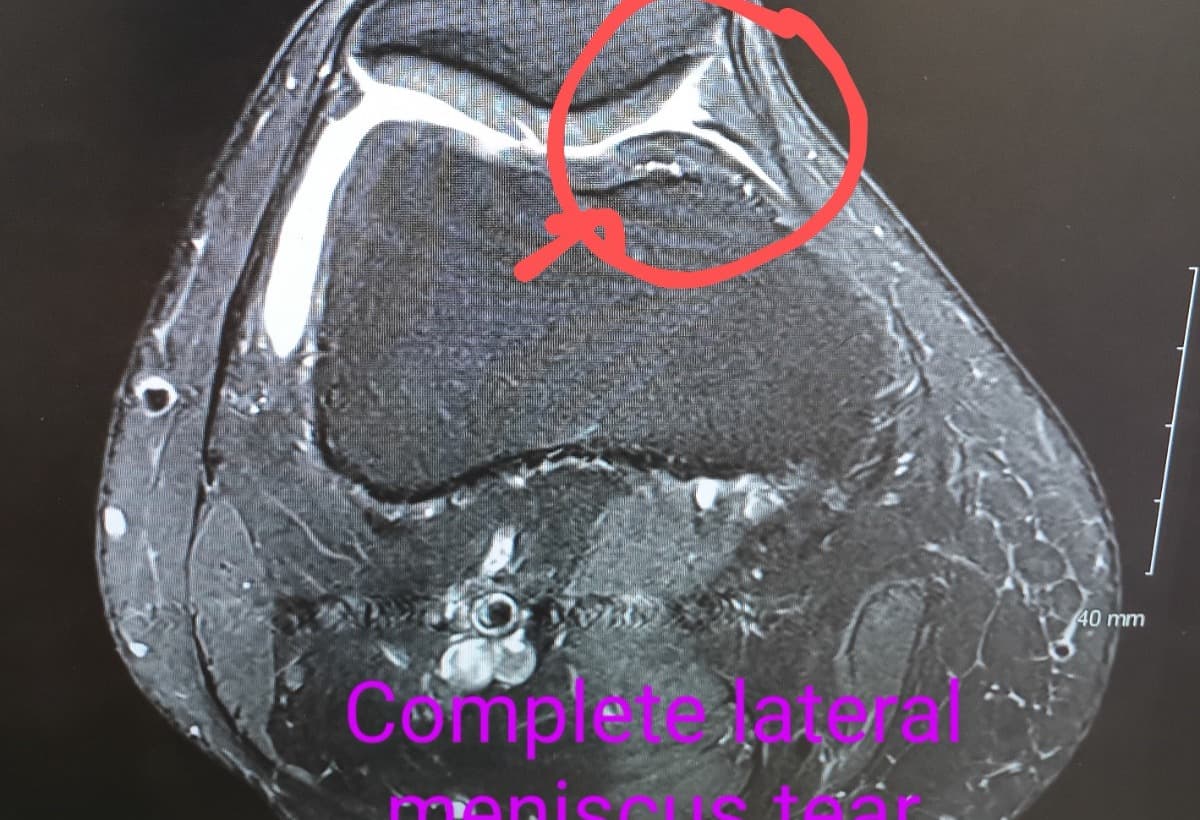

My name is Alika Brookes Rose. I am a 42 year old, single Mom of two teenage daughters. I have a PRESSING issue. Just got told by new Orthopedic that I need a 2 part surgery to harvest new cartilage and find a meniscus match because mine is 100% torn. Insurance is going to make me pay 20%, and I cant turn to my parents as they have helped far beyond what they even should have. Please, I understand that everyone has their own shit, REALLY I GET IT, but I am OUT OF options, treading water with Medical bills, and putting myself out here to get some help please. I absolutely hate borrowing money, let alone asking for help.